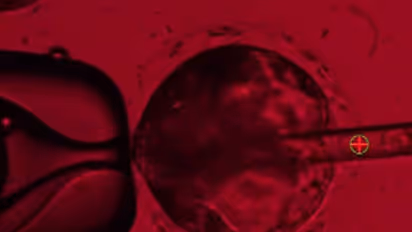

According to Zernicka-Goetz, the embryo-like structures were developed from a single human embryonic stem cell that was encouraged to differentiate into three separate tissue layers. They consist of cells that would ordinarily grow into the embryo itself, the placenta, and the yolk sac.